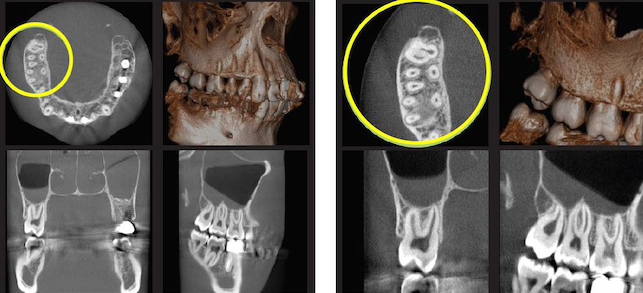

Esta nueva tecnología incorpora herramientas de gran utilidad tanto en 2D como en 3D. Por ejemplo, traza tanto el conducto dentario como la curva CMPR y la doble curva CMPR e inserta elementos en la imagen simulando implantes dentales. Además, permite la posibilidad de solicitar un visor zoom para reconstrucción de un estudio ya realizado, con el fin de observar zonas en más detalle de volumen de gran tamaño.

Gracias a la tecnología pionera de este escáner y a la calidad de la imagen proporcionada, los diagnósticos podrán ser mucho más precisos. En su aplicación clínica posibilita desde planificar un caso de rehabilitación total con implantes hasta la detección de un cuarto conducto en endodoncia.